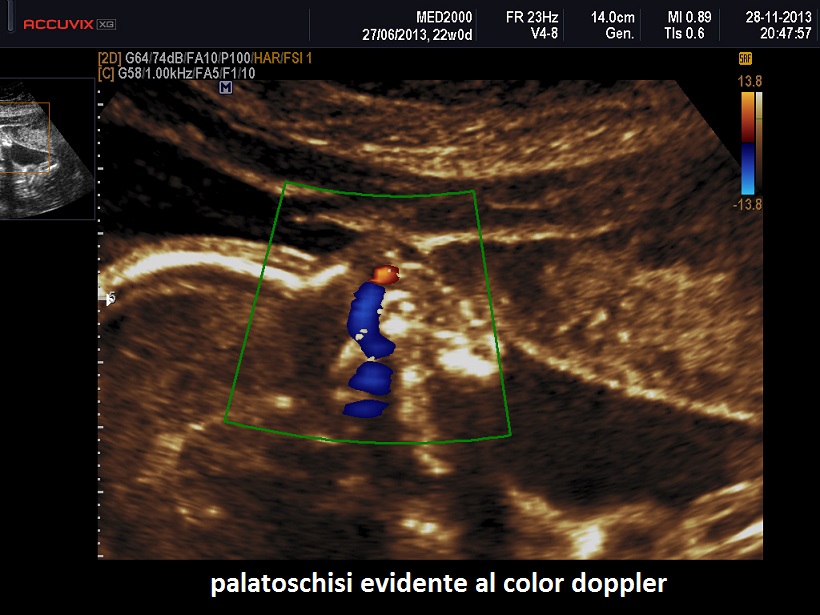

E' una displasia scheletrica caratterizzata da nanismo rizomelico con incurvamento del femore e della tibia. Si associano dismorfismo facciale (con micrognazia e palatoschisi), ipoplasia toracica  con coste corte (di solito sono presenti 11 paia di coste), ambiguità dei genitali fino al sex reversal (cariotipo maschile con fenotipo femminile); frequente è l'ipoplasia della fibula; si evidenzia inoltre piede torto, idrocefalia, macrocefalia.